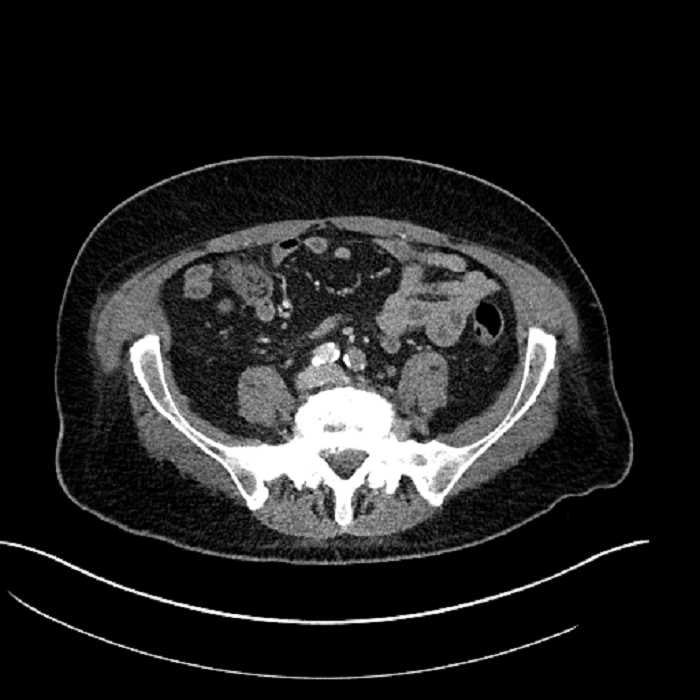

• Large fluid density structure in hepatic segments 7 and 8 measuring 10 x 7 x 7 cm with internal septation and circumferential ill-defined low density compatible with edema

• Peripherally enhancing subcapsular collections along the anterior margin of the left hepatic lobe measuring 3 x 1 cm and 2 x 1 cm

• Mild mural thickening of a segment of the sigmoid colon with adjacent fat stranding and a 1.5 cm fluid and gas collection along the tip of an inflamed diverticulum

• Loss of the normal fat plane between this collection and adjacent loops of small bowel, which demonstrate mural thickening

Acute sigmoid diverticulitis complicated by a small contained perforation and a large abscess in the right hepatic lobe. Additional small subcapsular abscesses along the anterior margin of the left hepatic lobe.

Additionally, loss of the normal fat plane between the peridiverticular collection and adjacent thickened loops of small bowel raises the potential for an enterocolonic fistula.

• The classic CT imaging appearance is a double target sign with internal low density surrounded by an internal enhancing rim (capsule) and a low density external rim (edema)

Hepatic abscess showing the double target sign with low density internally surrounded by a thin inner enhancing rim (red arrow) and ill-defined outer low density rim (yellow arrow). Blue arrow indicates an internal septation. Red arrows: additional smaller subcapsular abscesses. Red arrow: focal contained perforation associated with diverticulitis.